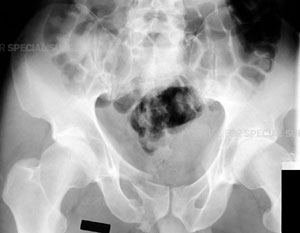

Radiograph of a normal pelvis

Radiograph of the pelvis demonstrating a fracture of the pubic bone